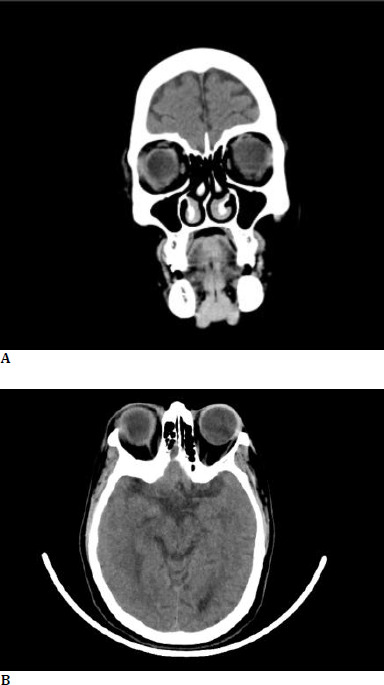

Material and methods: A 55-year-old female, with a history of diabetes and hypertension, developed bilateral eye pain, redness, and photophobia two days after taking oral Ibandronate for a thoracic spine fracture. Examination revealed reduced visual acuity, anterior uveitis at presentation, and bilateral proptosis two days later. The imaging revealed diffuse bilateral orbital inflammation.